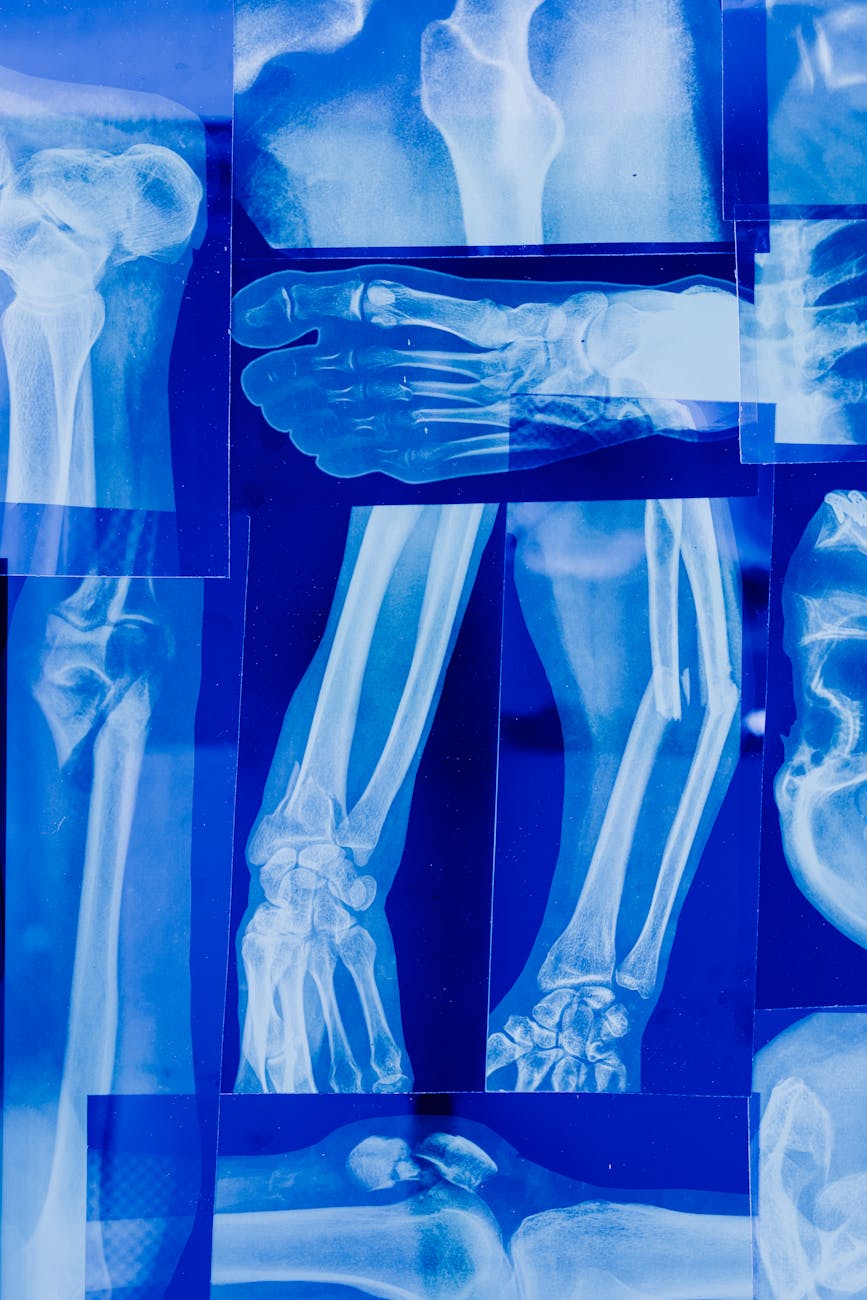

Photo by Tara Winstead on Pexels

Artificial intelligence is poised to revolutionize medical imaging, driving substantial market expansion. Experts predict a compound annual growth rate (CAGR) of roughly 29% for the global AI in medical imaging market through 2032. This surge is fueled by the healthcare industry’s embrace of AI-powered solutions, promising enhanced diagnostic capabilities and optimized treatment strategies. A discussion of this trend can be found online: [https://old.reddit.com/r/artificial/comments/1oukyye/global_ai_in_medical_imaging_market_to_anticipate/]